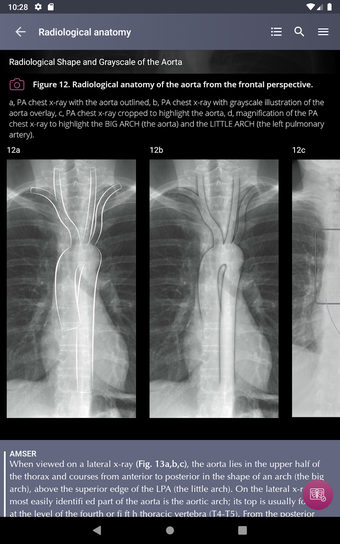

Radioloji'yi Keşfet: Göğüs Röntgeni Yorumlama, göğüs röntgeninin yorumlanmasının anlaşılmasını artırmak için tasarlanmış bir eğitim uygulamasıdır ve doktorlar, tıp öğrencileri ve radyologlar tarafından kullanılması amaçlanmaktadır. Uygulama, en küçük detayları görüntülemek için yakınlaştırılabilecek yüksek kaliteli görüntüler ve her bulgunun önemini anlamanıza yardımcı olacak bir sesli yorum içerir.

Uygulamanın amacı, kullanıcıların farklı x-ışını bulgularını ve bunların bir hastalığın teşhisinde nasıl kullanılabileceğini daha iyi anlamalarına yardımcı olmaktır. Uygulama, göğüs röntgeni yorumlaması için gerekli çeşitli yapı taşlarını kapsayan 5 bölüme ayrılmıştır.